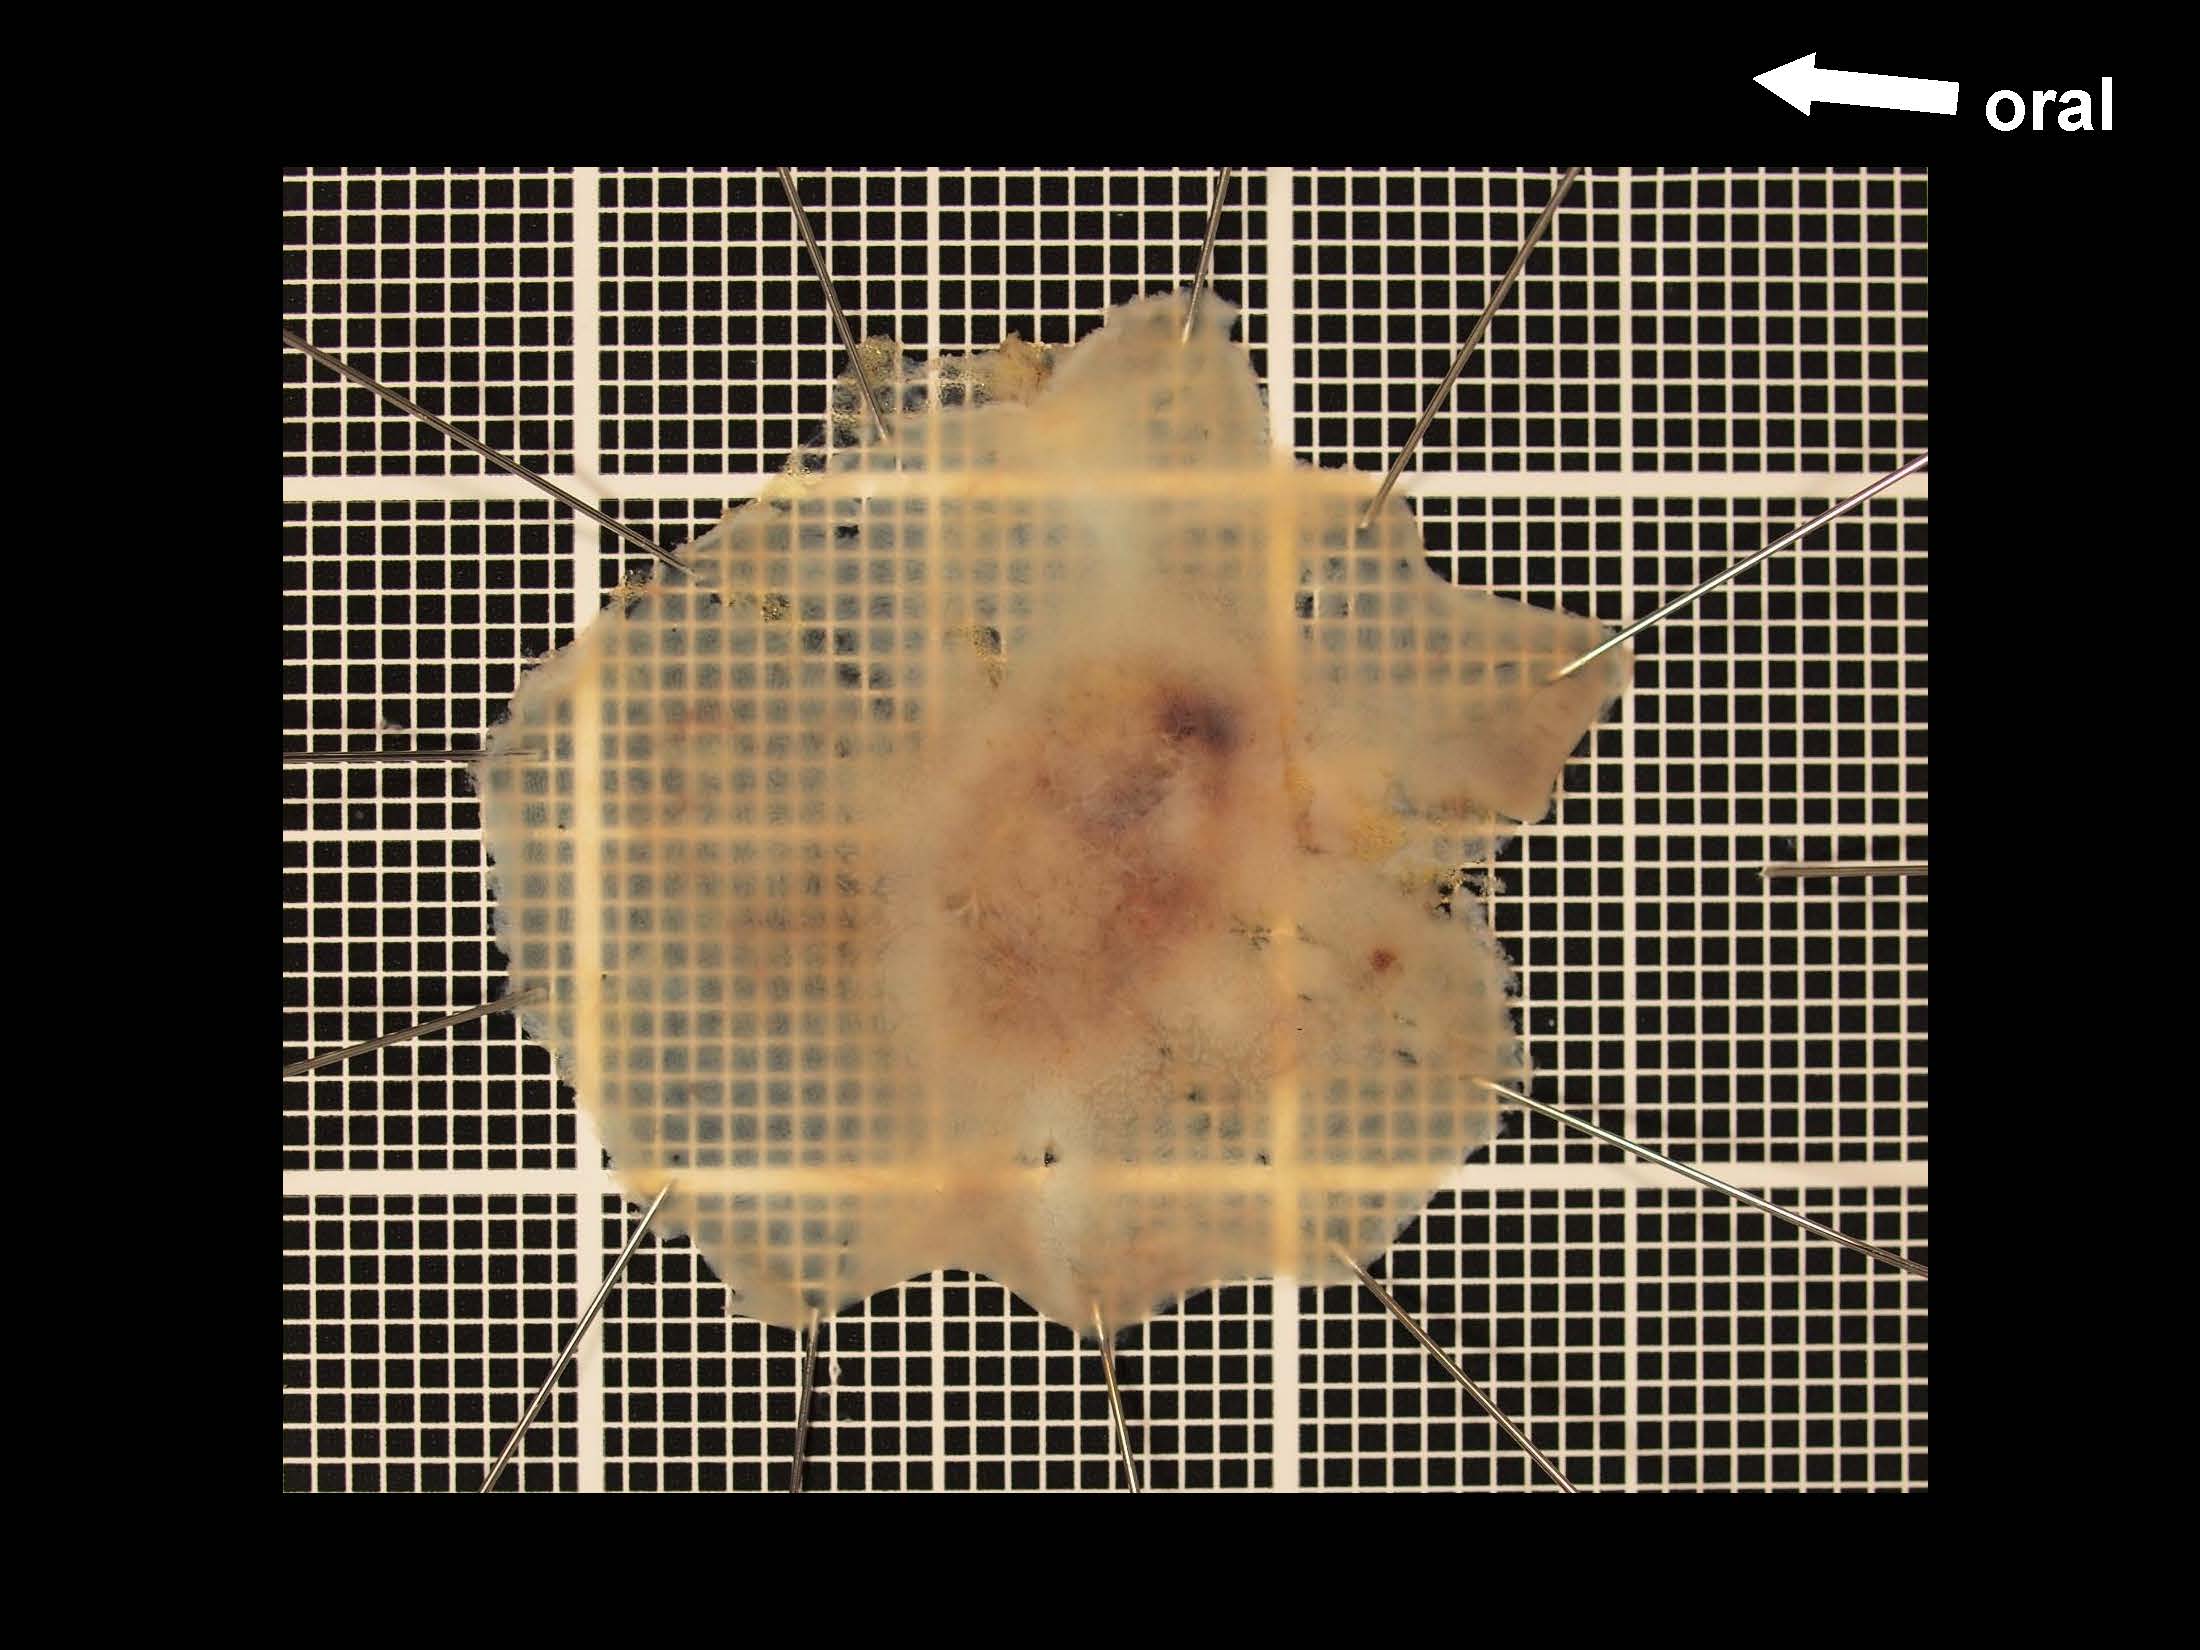

消化管Mapping~大腸~ 2021.10.27

消化管Mapping

消化管Mapping~大腸~

消化器内科

内視鏡検査・治療